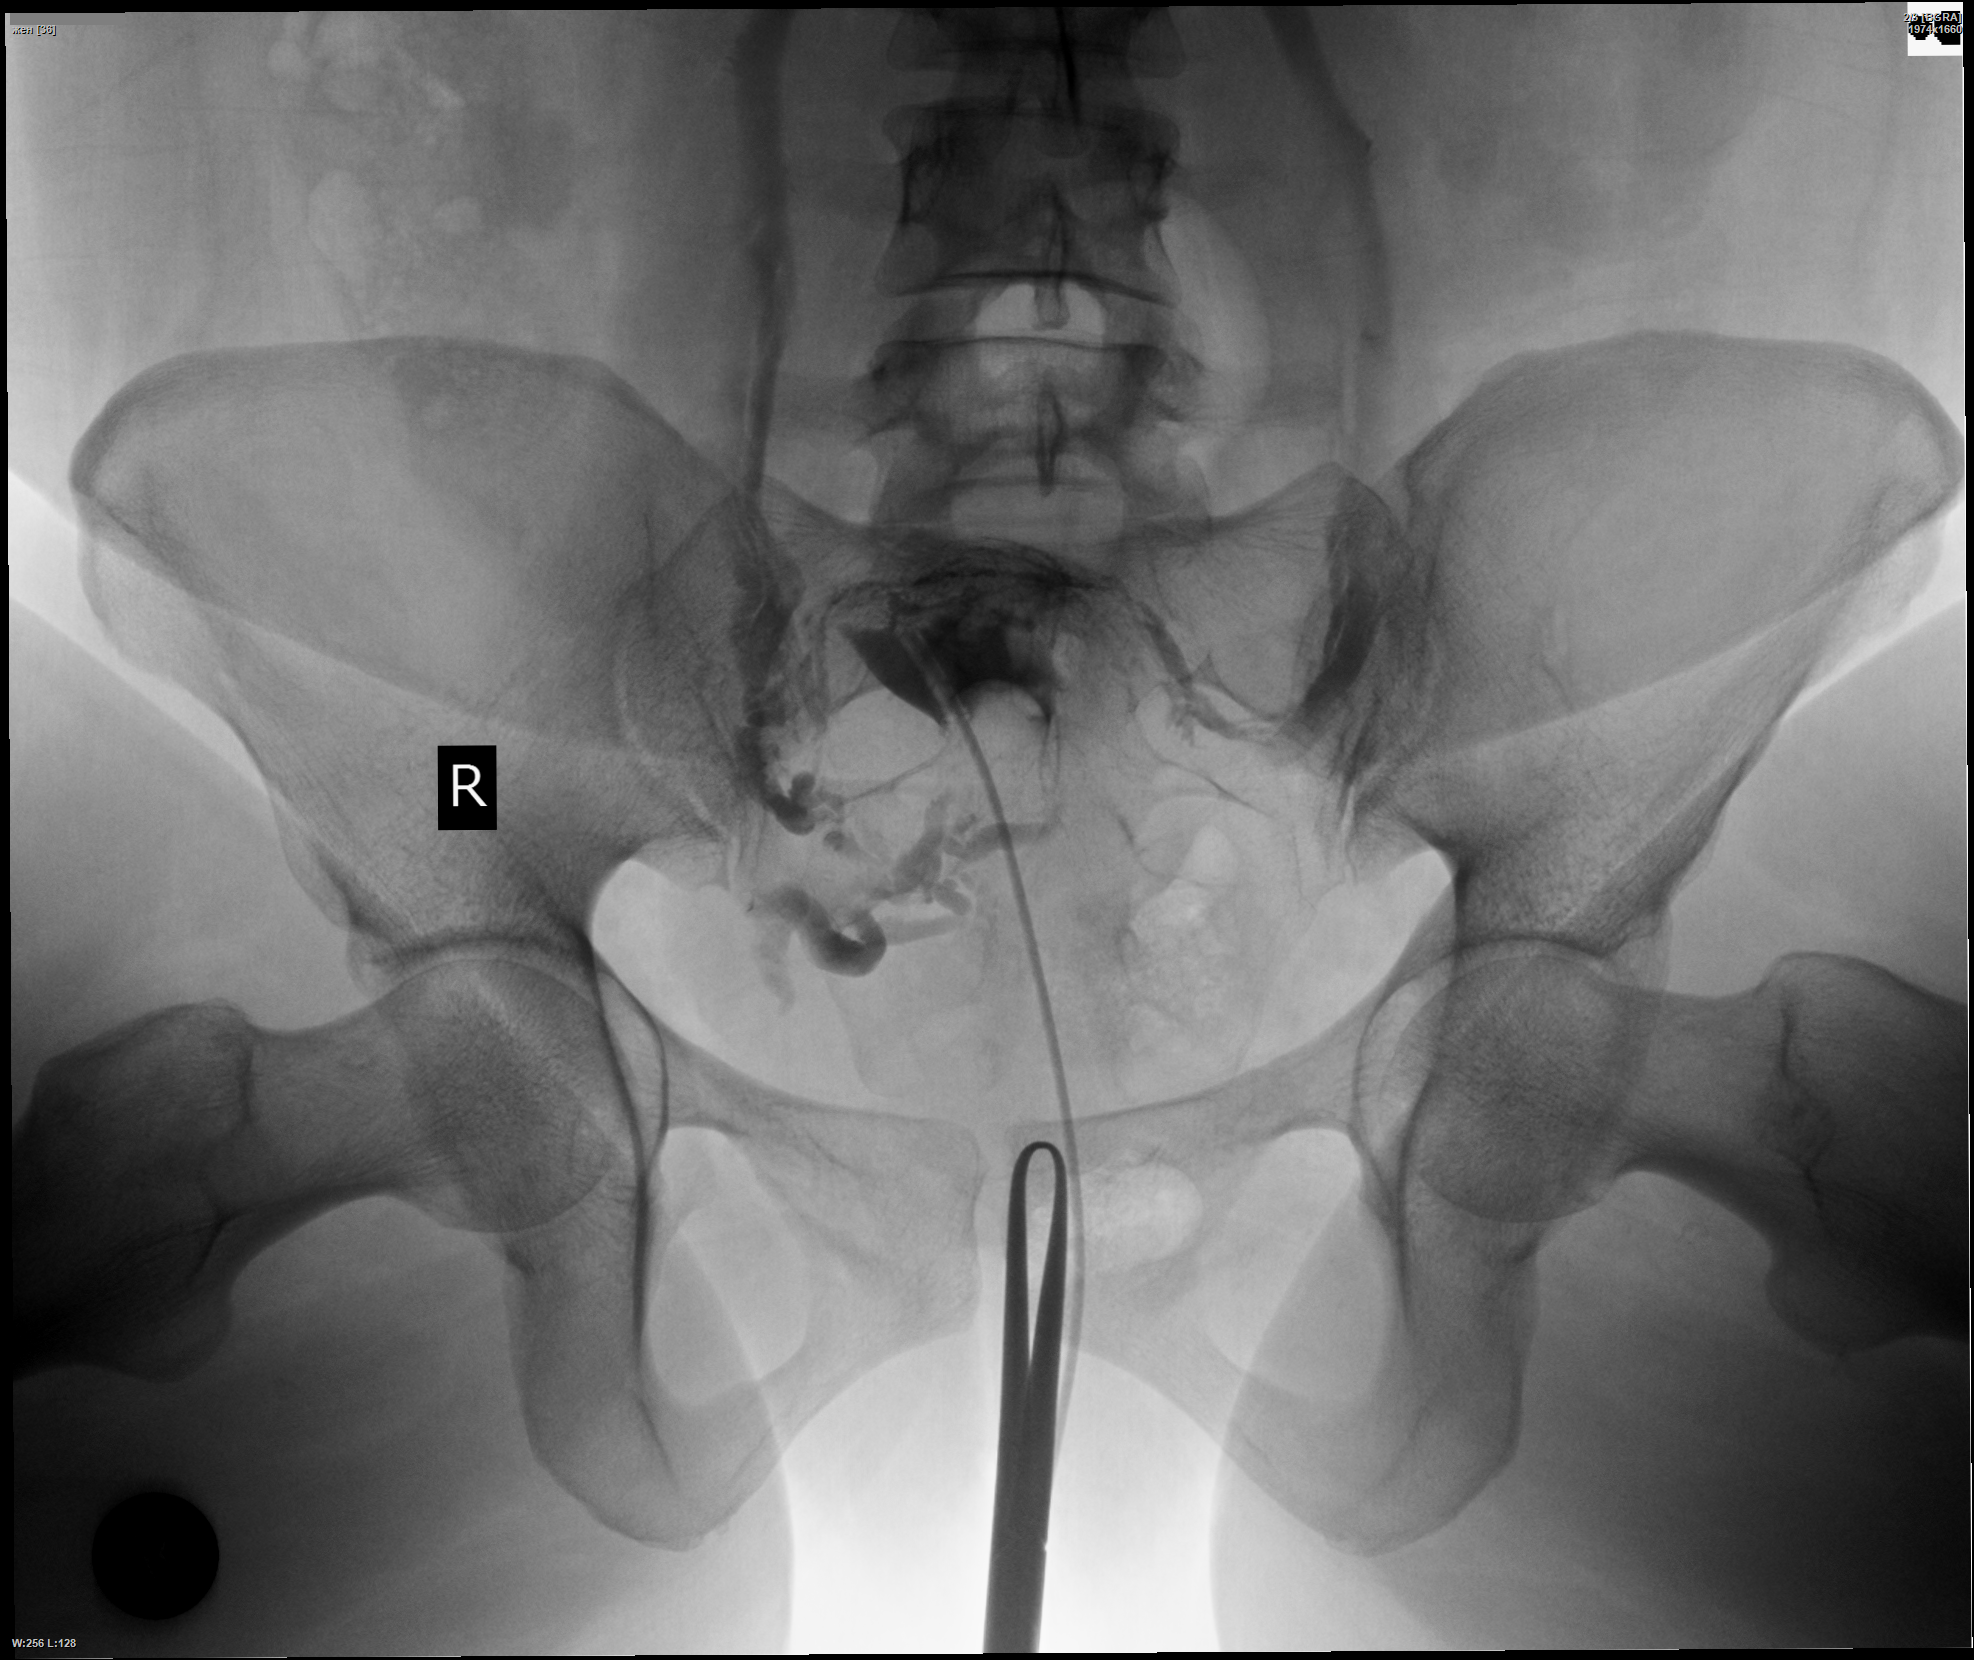

Гистеросальпингография: описание и фотографии